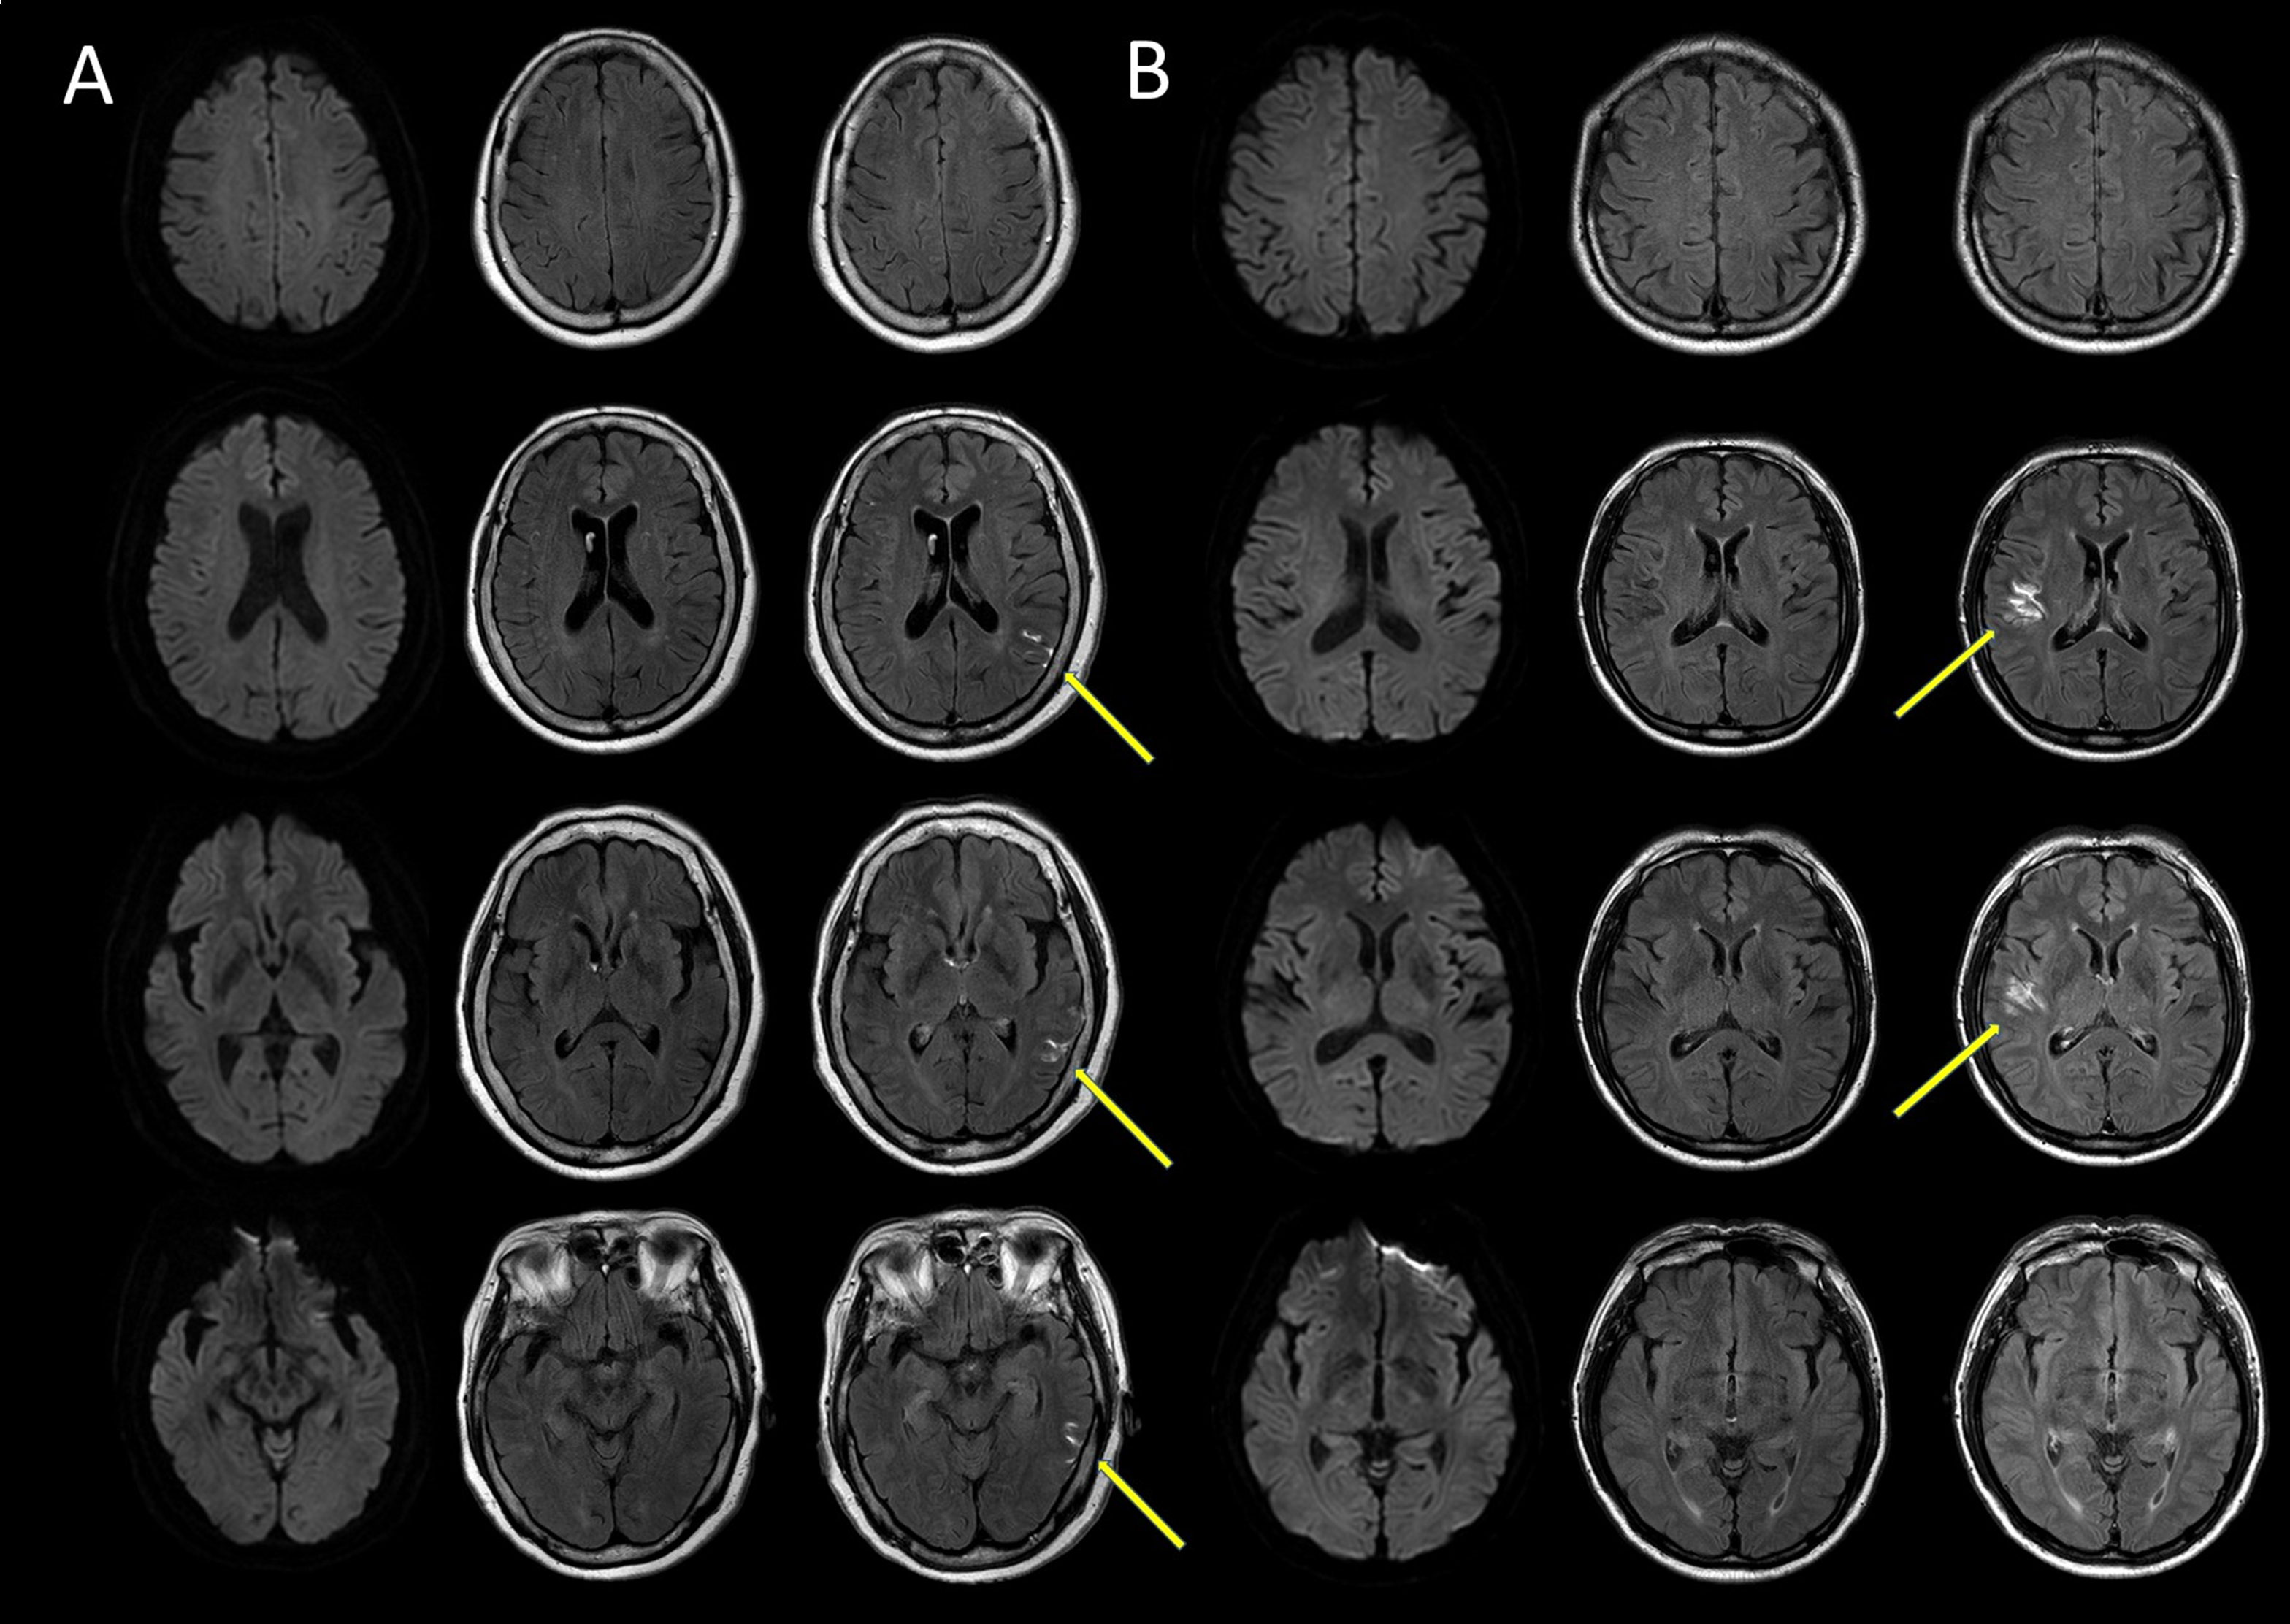

Abstract Body: Background: The hyperintense acute reperfusion marker (HARM) sign is a hyperintense signal observed on postcontrast fluid-attenuated recovery inversion images and is strongly associated with cerebral ischemic insults. The clinical significance of the HARM sign in transient ischemic attack (TIA) has rarely been studied, unlike that in stroke. This study investigated the relationship between the HARM sign and various clinical factors in diffusion-weighted imaging (DWI)-negative TIA. Furthermore, we investigated the relationship between the HARM sign with recurrence of TIA and ischemic stroke.

Methods: We included 329 consecutive patients with DWI-negative TIA and divided them into two groups according to the HARM sign: 299 patients in the HARM(-) group and 30 patients in the HARM(+) group. Clinical information, brain imaging, and follow-up data were gathered from medical records and phone calls and compared using the HARM sign.

Results: The patients with HARM sign were older (70.7 vs. 64.4 years, p = 0.007), had more previous TIA or stroke history within 12 months (26.7% vs. 4.0%, p < 0.001), and had higher systolic blood pressure (154.3 vs. 144.1, p = 0.022). The HARM(+) group also had a shorter symptom duration of <1 hour (63.3% vs. 38.8%, p = 0.009) and more symptomatic stenosis (50–99%) or occlusion (60.0% vs. 14.0%, p < 0.001). Among the transient neurological symptoms, only cortical symptoms were more prevalent in the HARM(+) group (30.0% vs. 8.7%, p = 0.002). The total follow-up duration of both groups was similar, and the Kaplan-Meier analysis showed a higher cumulative incidence of recurrent stroke in the HARM(+) group (log-rank test, p = 0.007). However, multivariate Cox analysis indicated that symptomatic stenosis or occlusion, rather than the HARM sign, was independently associated with stroke recurrence.

Conclusion: The HARM sign in DWI-negative TIA patients is linked to older age, recent cerebrovascular events, shorter symptom duration, and large artery stenosis or occlusion. While the HARM sign correlates with higher recurrence of ischemic stroke, large artery stenosis or occlusion is the primary independent predictor.